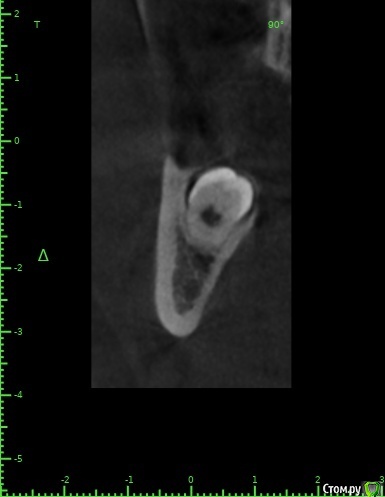

zumanok Опубликовано 15 февраля, 2021 Поделиться Опубликовано 15 февраля, 2021 Коллеги достаточно часто встречаюсь с такой картинкой на КТ в области ментального отверстия . Считаете ли вы это частью тройничного нерва или не обращать внимания? Ссылка на комментарий

Doctor Vlad Опубликовано 15 февраля, 2021 Поделиться Опубликовано 15 февраля, 2021 Коллеги достаточно часто встречаюсь с такой картинкой на КТ в области ментального отверстия . Считаете ли вы это частью тройничного нерва или не обращать внимания там что угодно может быть, больше похоже на пору кости. в этом случае до канала далеко. вы же не собираетесь так глубить? Ссылка на комментарий

zumanok Опубликовано 15 февраля, 2021 Поделиться Опубликовано 15 февраля, 2021 (изменено) там что угодно может быть, больше похоже на пору кости. в этом случае до канала далеко. вы же не собираетесь так глубить?Интересно может быть такая форма канала или стоит взять винт подлиньше? Примерно так и собирался, мб на пол мм выше. Объясните пожалуйста почему не стоит? Кроме того что коронка на 1 мм подлиньше будет. Изменено 15 февраля, 2021 пользователем zumanok Ссылка на комментарий

Doctor Vlad Опубликовано 16 февраля, 2021 Поделиться Опубликовано 16 февраля, 2021 Интересно может быть такая форма канала или стоит взять винт подлиньше? Примерно так и собирался, мб на пол мм выше. Объясните пожалуйста почему не стоит? Кроме того что коронка на 1 мм подлиньше будет.скорей всего там нерва нет и это не канал. Но. А если есть)? Ссылка на комментарий

zumanok Опубликовано 16 февраля, 2021 Поделиться Опубликовано 16 февраля, 2021 (изменено) скорей всего там нерва нет и это не канал. Но. А если есть)?Да вот,для этого и выбрал 3.5 на 8.5. Сам склоняюсь к тому что костный рисунок, информации о таком строении нерва не нашел. Думаю в процессе препарирования ложа посмотреть, если будет чувствительность то не лезть дальше.Подскажите чем Вас смутила глубина установки имплантата? Только этим образованием?По КТ 1.5мм до него. Изменено 16 февраля, 2021 пользователем zumanok Ссылка на комментарий

Raystom Опубликовано 16 февраля, 2021 Поделиться Опубликовано 16 февраля, 2021 Там будет не чувствительность, а резкий провал фрезы после определенного момента препарирования, если не отслеживать момент с глубиной, чем напугаете и себя и пациента. По поводу рисунка может быть как и костный рисунок, так и петля нижнелуночкого канала, зачем проверять? Ссылка на комментарий

Doctor Vlad Опубликовано 16 февраля, 2021 Поделиться Опубликовано 16 февраля, 2021 Да вот,для этого и выбрал 3.5 на 8.5. Сам склоняюсь к тому что костный рисунок, информации о таком строении нерва не нашел. Думаю в процессе препарирования ложа посмотреть, если будет чувствительность то не лезть дальше.Подскажите чем Вас смутила глубина установки имплантата? Только этим образованием?По КТ 1.5мм до него.как он нарисован норм, длиннее не стал бы, чтобы запас был. Просто, по вашим фото не совсем видно где канал. иногда и по кт все очень смутно. особенно когда огромные поры. Ссылка на комментарий

Nazim_NV86 Опубликовано 16 февраля, 2021 Поделиться Опубликовано 16 февраля, 2021 Просто пора. Меня больше размер 3.5-8.5 смущает. Я бы отогнул вогнутую вестибулярную часть и поставил. Заодно и десны мб накинул. Ссылка на комментарий

zumanok Опубликовано 16 февраля, 2021 Поделиться Опубликовано 16 февраля, 2021 (изменено) Там будет не чувствительность, а резкий провал фрезы после определенного момента препарирования, если не отслеживать момент с глубиной, чем напугаете и себя и пациента. По поводу рисунка может быть как и костный рисунок, так и петля нижнелуночкого канала, зачем проверять?Благодарю за ответ. Проверять не собираюсь, ставить буду по шаблону поэтому и выбрал этот размер что бы не задеть. Но решил уточнить правильно ли я делаю или все таки таких вещей не стоит остерегаться. как он нарисован норм, длиннее не стал бы, чтобы запас был. Просто, по вашим фото не совсем видно где канал. иногда и по кт все очень смутно. особенно когда огромные поры.Длиннее не буду. Спасибо. Но все таки докопаюсь до Вас . Чем Вас смутило само заглубление? Очень глубоко? Просто пора. Меня больше размер 3.5-8.5 смущает. Я бы отогнул вогнутую вестибулярную часть и поставил. Заодно и десны мб накинул. Меня немного тоже. Думал поставить 4х8.5 но как то совсем в притык получается. Параллельно в области 4.6 буду ставить 4,5х10 планирую их спаять. Поидее проблем быть не должно. ССТ у 4.5.вестибулярно. Изменено 16 февраля, 2021 пользователем zumanok Ссылка на комментарий

Nazim_NV86 Опубликовано 17 февраля, 2021 Поделиться Опубликовано 17 февраля, 2021 Меня немного тоже. Думал поставить 4х8.5 но как то совсем в притык получается. Параллельно в области 4.6 буду ставить 4,5х10 планирую их спаять. Поидее проблем быть не должно. ССТ у 4.5.вестибулярно.1. Смотря какая протетика потом будет. Если будет абатмент без 6гр оригинал( хоть винтовую делайте на нём), то не парьтесь - ставьте 3.5 и связывайте. Если всякая дребедень, типа премилов, оснований, то рискуете увидеть перелом шейки. Тогда см. 22. Базальная часть челюсти весьма широкая. Тут даже НКР+имплант на ура зайдёт. Как я уже писал, отогнуть фрагмент и поставить хоть 4.5 можно. Это мой субъективный опыт. Ссылка на комментарий